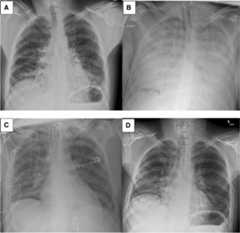

His vital signs on presentation were a temperature of 38°C, heart rate of 104 beats per min in sinus rhythm, and blood pressure of 147/88 mm Hg. His initial oxygen saturation (SpO2) was 90% on room air but he quickly progressed to needing a fraction of inspired oxygen of 80% via high flow nasal cannula to attain a SpO2 of 90–94%. A chest radiograph showed diffuse reticular nodular opacities throughout both lungs (Fig.1). His initial bloodwork showed signs of elevated inflammatory markers with mild leukocytosis at 11.1 × 109·L-1 (normal, 4.0–10.5 × 109·L-1) and C-reactive protein of 218.4 mg·L-1 (normal, 0.0–2.0 mg·L-1) but other results were noncontributory. His urine drug screen was positive for amphetamines, cocaine, fentanyl, and opioids. Due to progressive hypoxemic respiratory failure, he was intubated and admitted to the intensive care unit (ICU). Three nasopharyngeal swabs and a tracheal aspirate sample were all negative for SARS-CoV-2. He was treated with intravenous piperacillin-tazobactam, azithromycin, and vancomycin as well as methylprednisolone 40 mg twice daily. A computed tomography (CT) scan of the chest was performed on day 3 of illness and revealed extensive bilateral ground-glass and centrilobular nodular opacities without evidence of pulmonary embolism (Fig.2).

Fig. 1.

Chestx-rays of the patient on day 1 of illness (A); day 5 of illness, before cannulation onto extracorporeal membrane oxygenation (ECMO) support (B); day 24 of illness, after decannulation from ECMO support (C); and day 34 of illness, after decannulation from tracheostomy (D)

His respiratory function improved over time. By day 24, his tidal volumes were up to 450 ml/breath while the same ventilatory settings, and ECMO support was weaned. He showed radiographic improvement (Fig.1). He was decannulated from vv-ECMO on day 26 of illness and liberated from the ventilator support and discharged from the ICU on day 28 of illness. He was discharged from ambulatory hospital care on day 50 of illness, requiring no oxygen and tolerating a full diet.